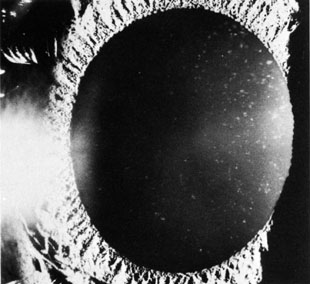

In advanced retinopathy of prematurity, tissue from the retinal periphery can extend to the retrolental area, and this fibrovascular tissue can form a pseudotumor. As this progresses, total retinal detachment, secondary hemorrhage, swelling and edema of the mass, and the development of posterior synechia can occur. The anterior chamber can become shallow, resulting in secondary angle-closure glaucoma. This has been noted to occur in approximately 2% of patients. Lens aspiration may be performed to relieve the forward displacement of the iris-lens diaphragm (Fig. 3), and iridectomy usually is necessary. This is often done for cosmetic purposes to prevent enucleation, as vision is usually poor because of the underlying retinal problems.

Fig. 3. Forward displacement of iris lens diaphragm and RLF (arrows indicate total central synechia).

Angle-closure glaucoma after photocoagulation for retinopathy of prematurity has been reported.26 Confluent laser photoablation also has been associated with cataracts and other complications,27 mostly related to anterior chamber ischemia.28 Overall, the incidence of cataract formation in patients who have undergone argon laser photocoagulation for retinopathy of prematurity is approximately 1%. The occurrence of cataracts may be higher when persistent hyaloidal vessels are present on the lens.26